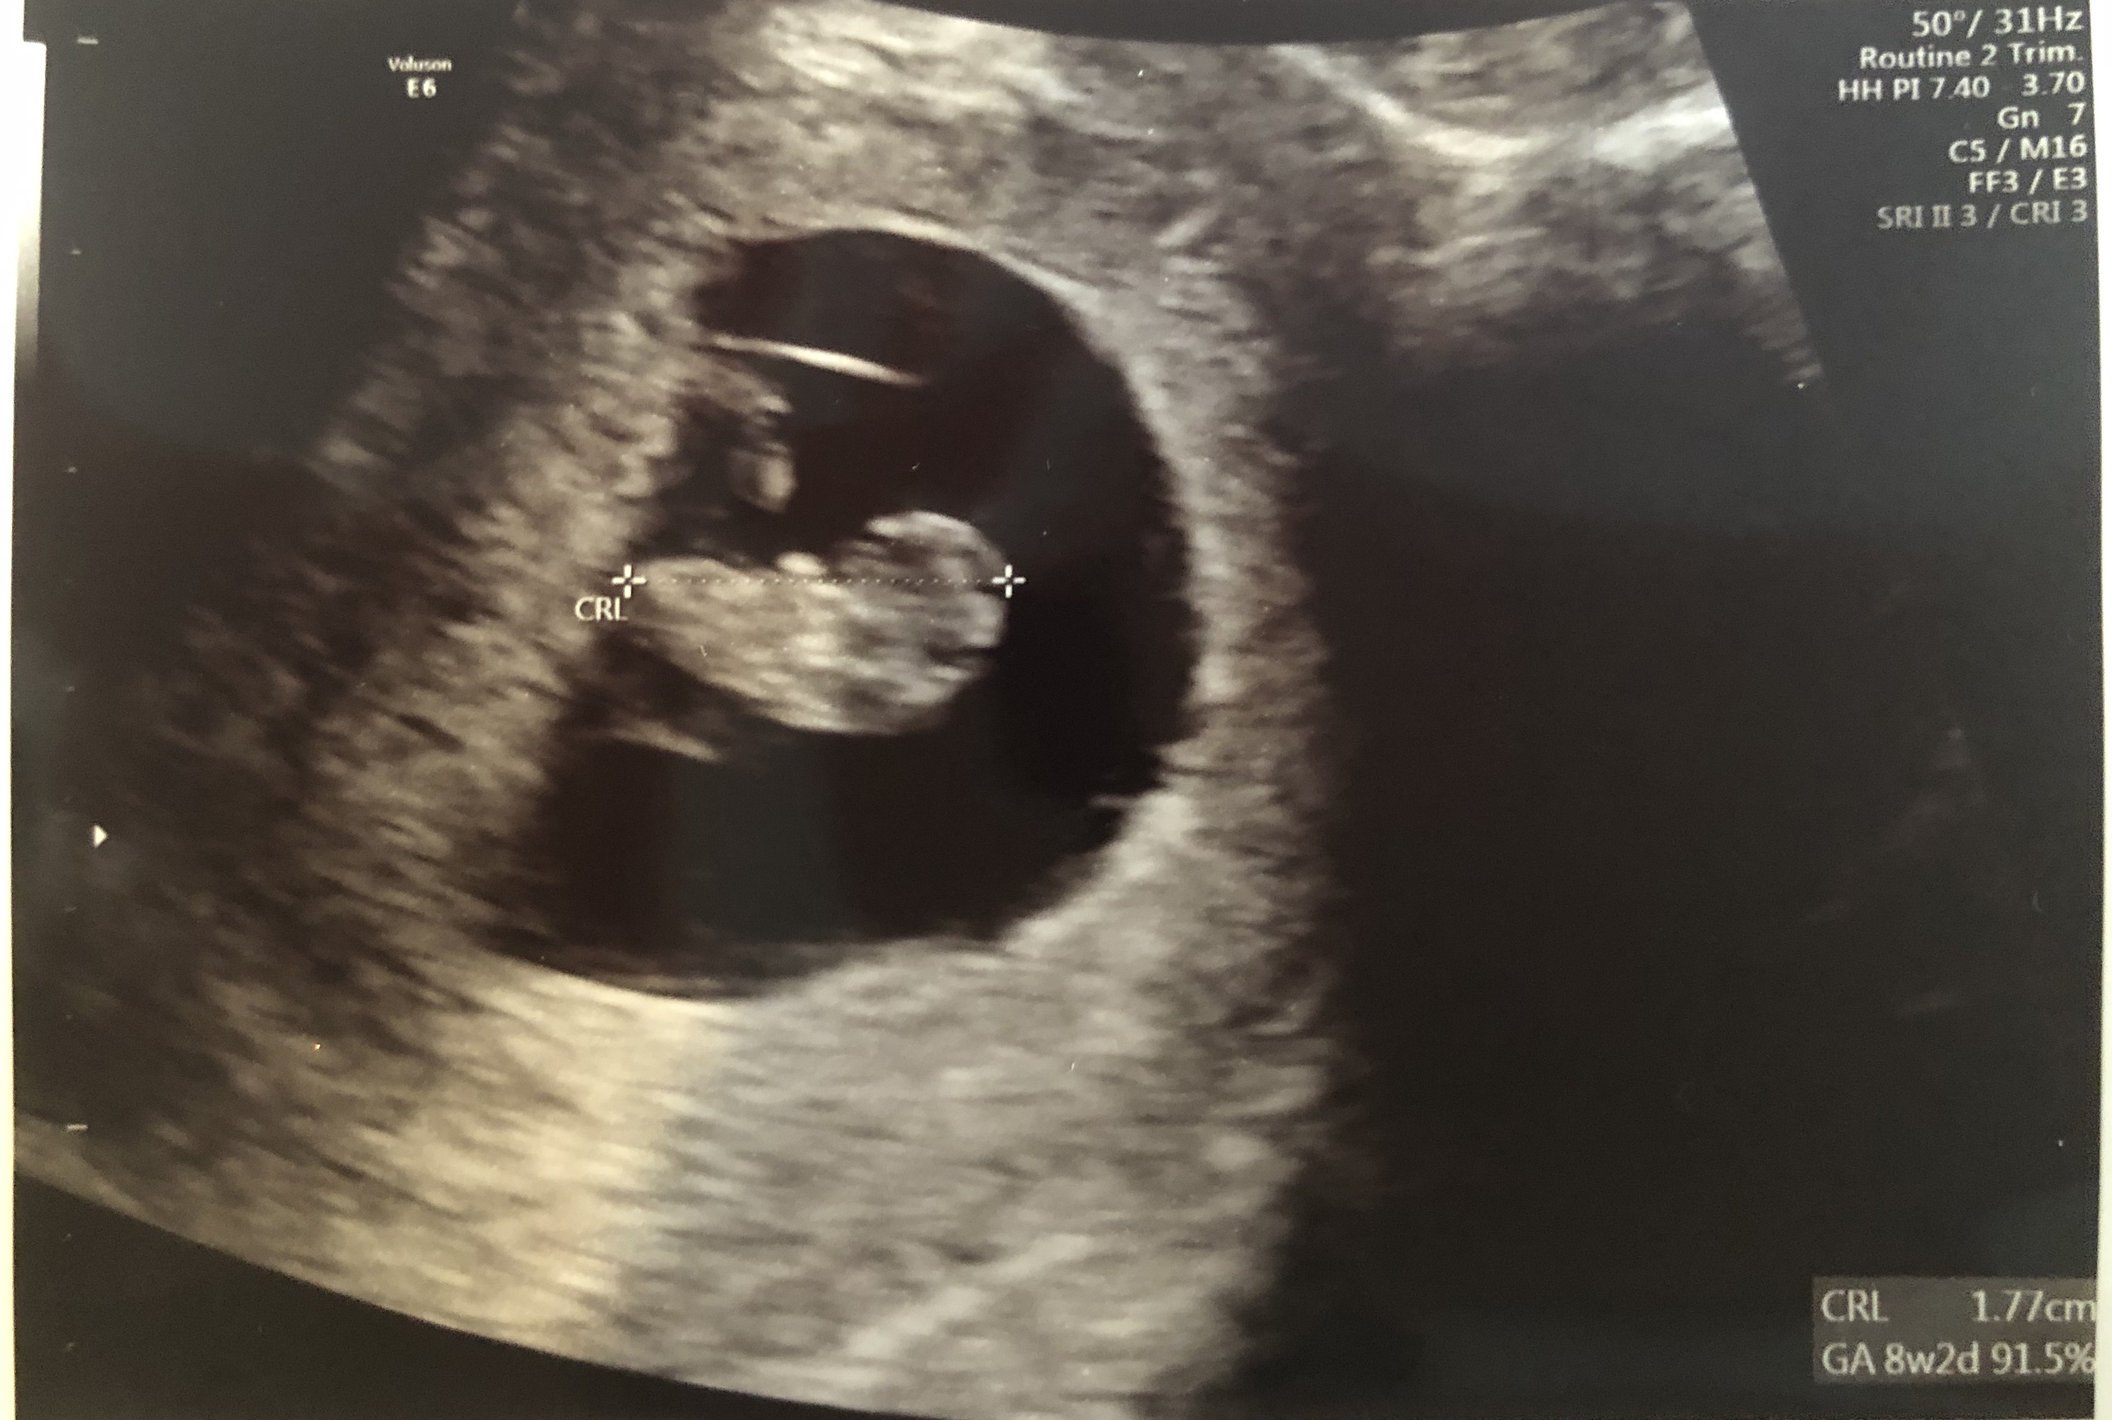

6w1d HB: 111 ♥️ little blob

Not too much to see but there's a little baby there with a heartbeat of 122 BPM